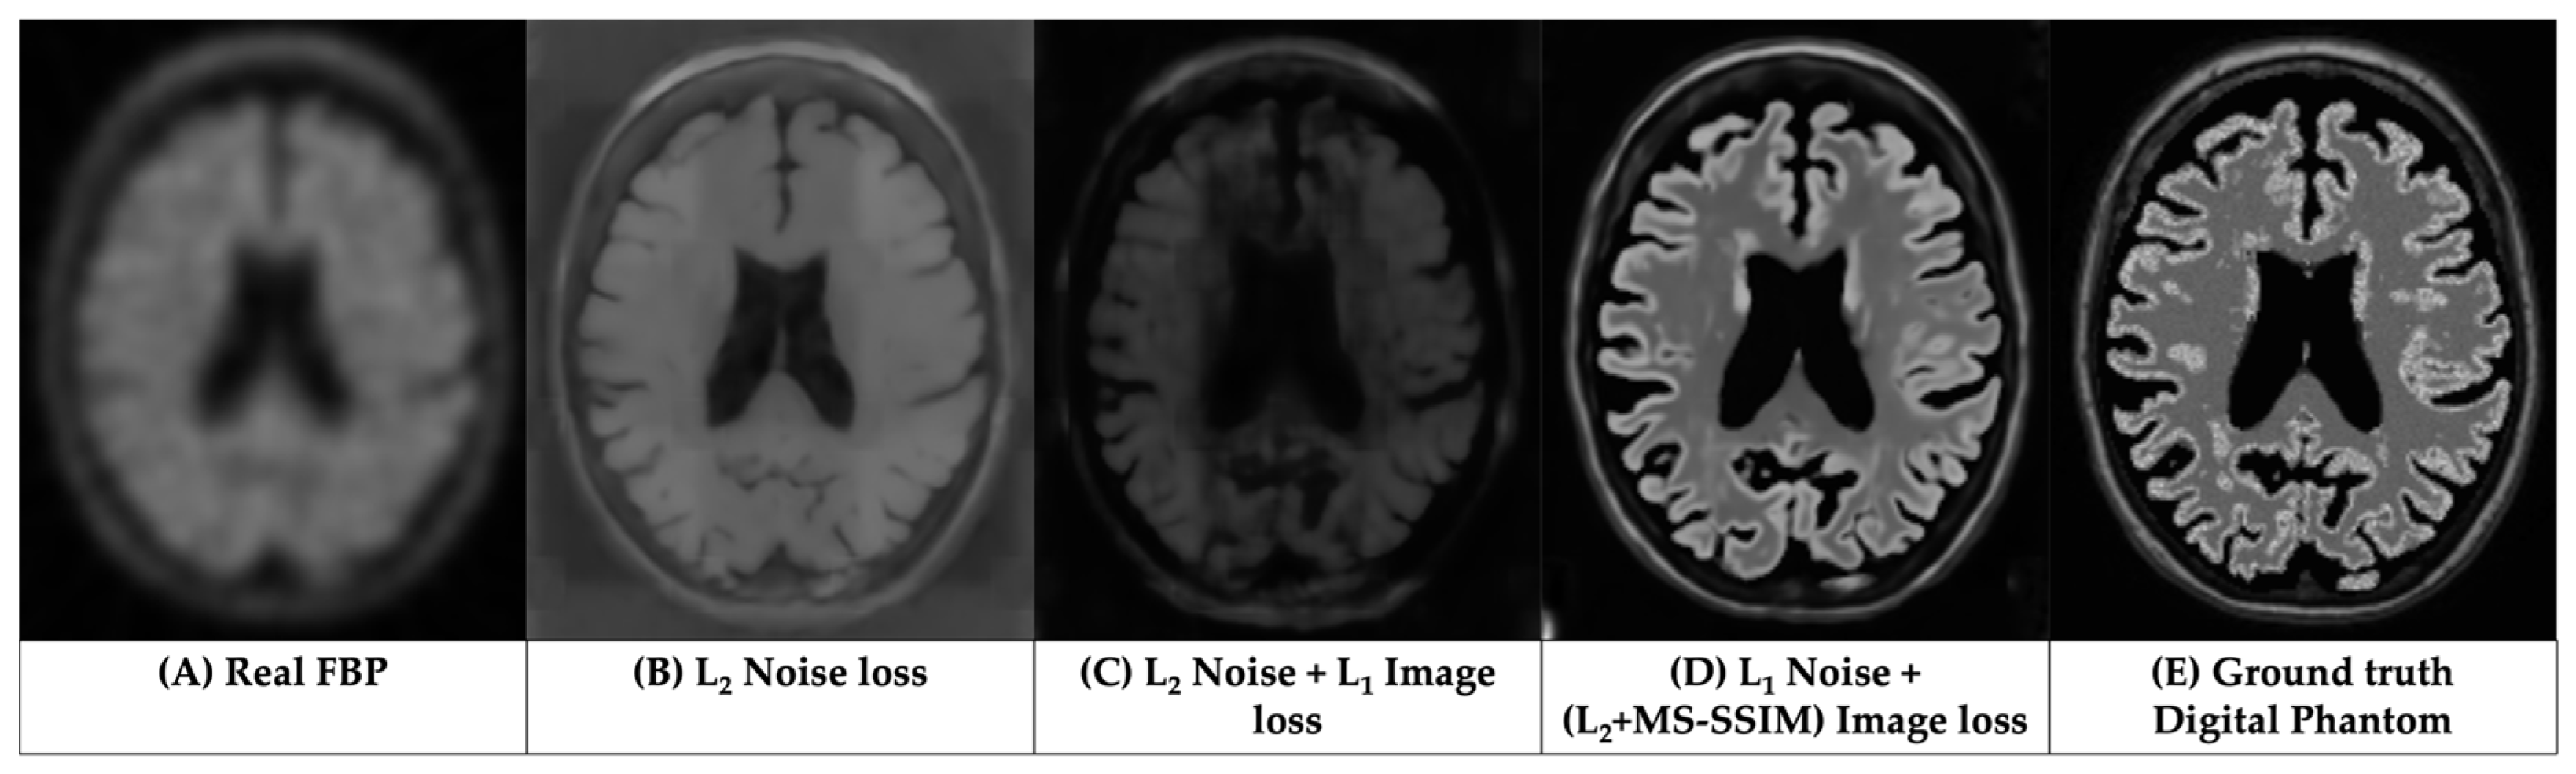

3.1. Qualitative Assessments